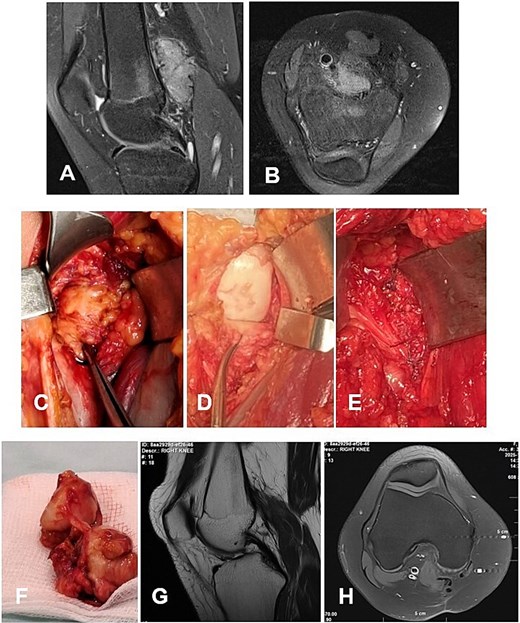

Case 1. (A and B) Preoperative T1 sagittal and axial MRI sequences with PD FS. (C and F) Macroscopic appearance of the pathological synovium before and after its excision. (D and E) The knee joint following synovectomy, demonstrating intact menisci and cruciate ligaments. Chondral lesions correspond to Outerbridge grade IV. (G and H) Postoperative 24 m. Sag and Ax MRI PD FS. No evidence of recurrence of the resected neoplasm was detected. Residual TGCT involvement persists within the lateral posterior femoral recesses. PD FS, proton density weighting with fat suppression; TSE, turbo spin echo.

A 4-year-and-5-month-old child presented with a history of chronic synovitis of the right knee joint persisting for more than 2 years. Progressive limitation of motion was observed—a 15° flexion contracture, and maximum flexion limited to 75°. Magnetic resonance imaging (MRI) was concordant with the intraoperative findings, demonstrating diffuse involvement of both anterior and posterior recesses of the knee joint (Fig. 2A–C). A subtotal anterolateral synovectomy was performed. Intraoperatively, chondral defects corresponding to Outerbridge grade IV were identified (Fig. 2C–E). At 2-year follow-up, a substantial improvement in the range of motion was achieved (Table 1). Follow-up MRI demonstrated no evidence of local recurrence in the previously resected area of the neoplasm (Fig. 2G–H). A secondary synovectomy is planned to address residual synovial involvement within the posterior lateral femoral recess.